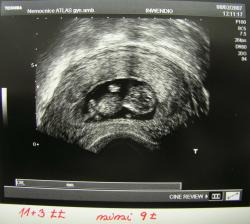

SRPŇÁTKA 2007 - fotky UTZ

album věnované mimískům, které se narodí v srpnu 2007 a jejich maminkám ze "Společného termínu SRPEN"